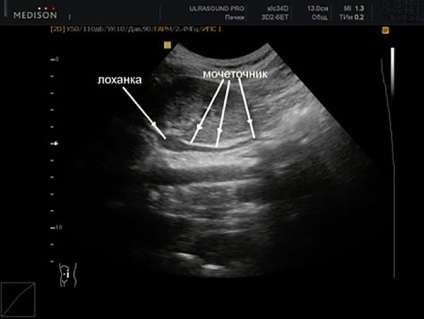

Együtt a vesék, az eljárás ultrahang technikus is értékelte az állam az ureter és vesemedence rendszer.

Normális ureter L között változik 25 és 30 cm-es, míg a átmérője kell lennie 09.06 mm. Rövid vagy rendellenesen hosszú húgyvezeték veleszületett rendellenesség. Húgyvezeték, amelynek hossza nagyobb, mint a norma, az a képessége, hogy kell csavarni, és ezáltal a stagnálás és a vizelettel, mint a fertőzés következtében a urogenitális rendszer.

Az ultrahang pyelocaliceal egészséges humán rendszerek medence és csészéket sem lehet láthatóvá (hiánya miatt echogenicitásának). Az ellenkezője május expanzió alatt és a medence jelzi patológia (például, urolithiasis vagy pyelonephritis).